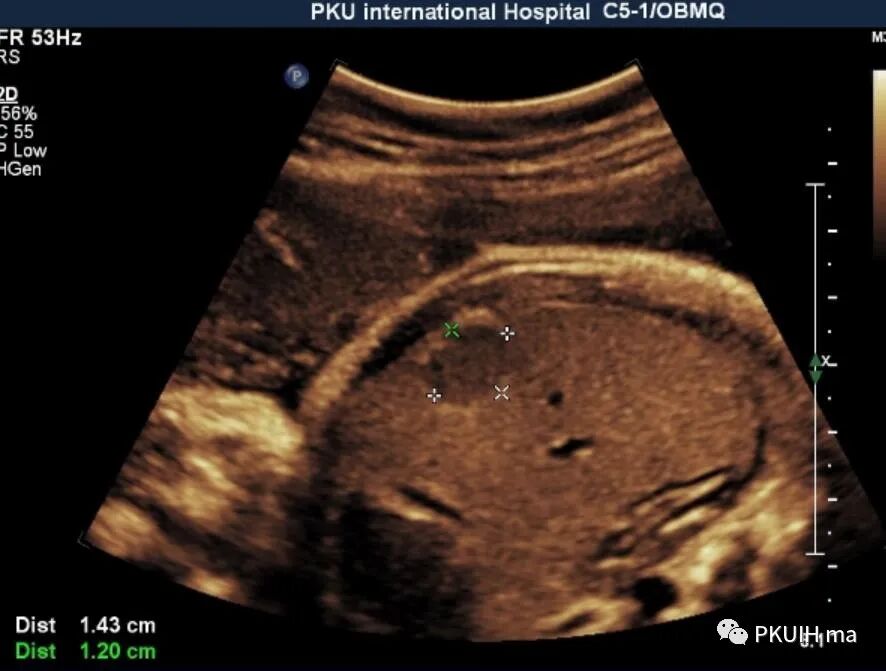

胎儿右肝内见一大小约1.4cm的实性低回声结节,边界清,形态规则,内回声均匀